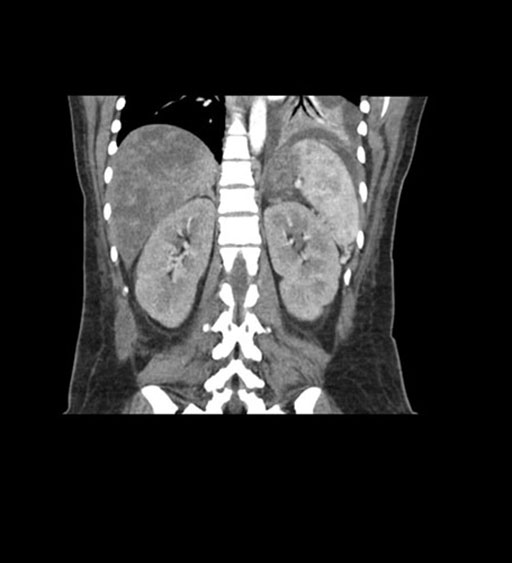

Coronal Arterial

Coronal Venous